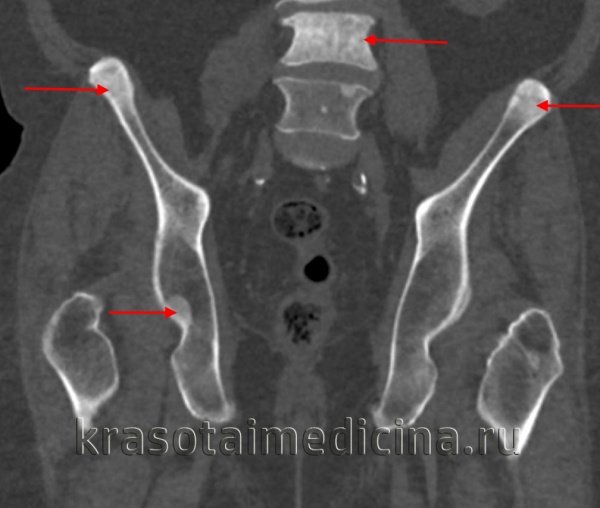

КТ таза. Множественные склеротические очаги в костях таза и позвонках вторичного опухолевого характера.